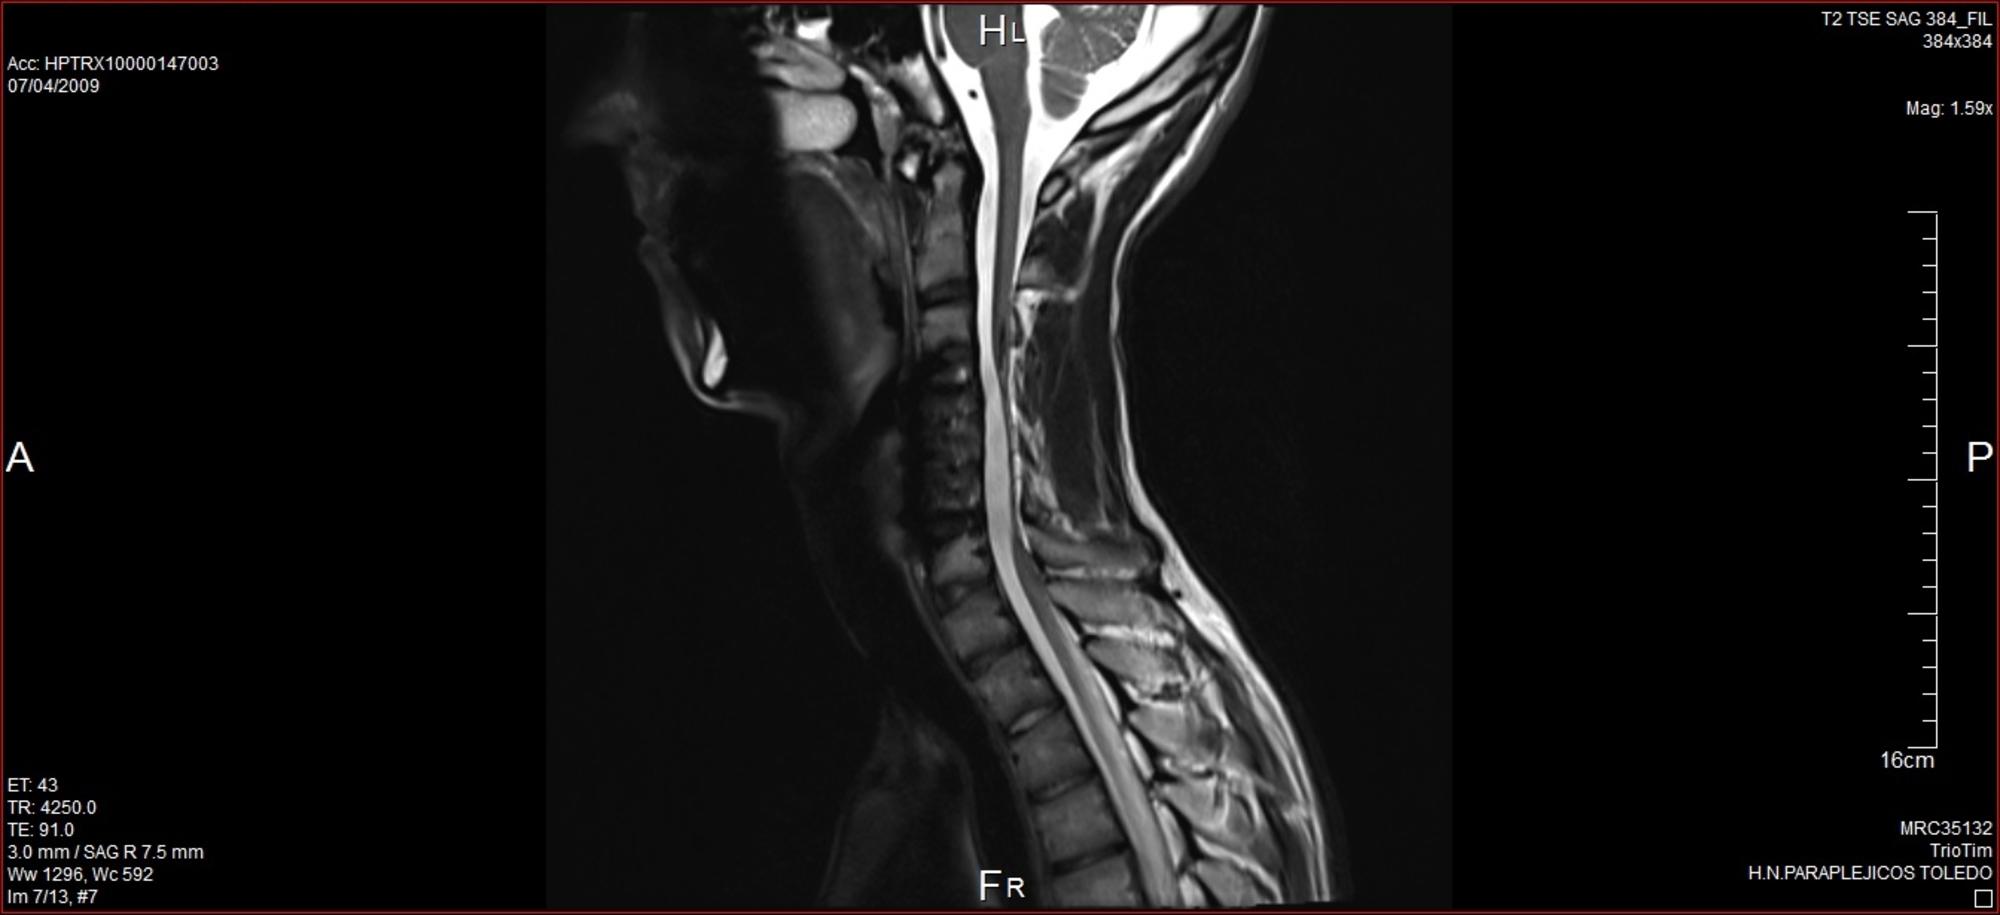

Hoy he querido traer una entrevista a una persona que con 17 años tuvo un accidente en el que se le rompieron las vértebras C5 y C6 y que le produjo una lesión medular aparentemente incompleta a ese nivel.

Como casi todas las personas con lesión medular en un primer momento fui trasladado al hospital de referencia de mi comunidad, donde me estabilizaron e intervinieron quirúrgicamente. Hasta ese momento el gasto más importante había sido el combustible del traslado diario de mi familia hasta el hospital pero, tras unas semanas, me llevaron al Hospital Nacional de Parapléjicos donde, además de la gravedad de la lesión medular, fuimos conscientes del enorme gasto que conllevaría. Durante los seis meses de hospitalización alquilamos un piso que costaba 700 euros, más todos los gastos diarios. Únicamente los seis meses en Toledo costaron en torno a 7200 euros.